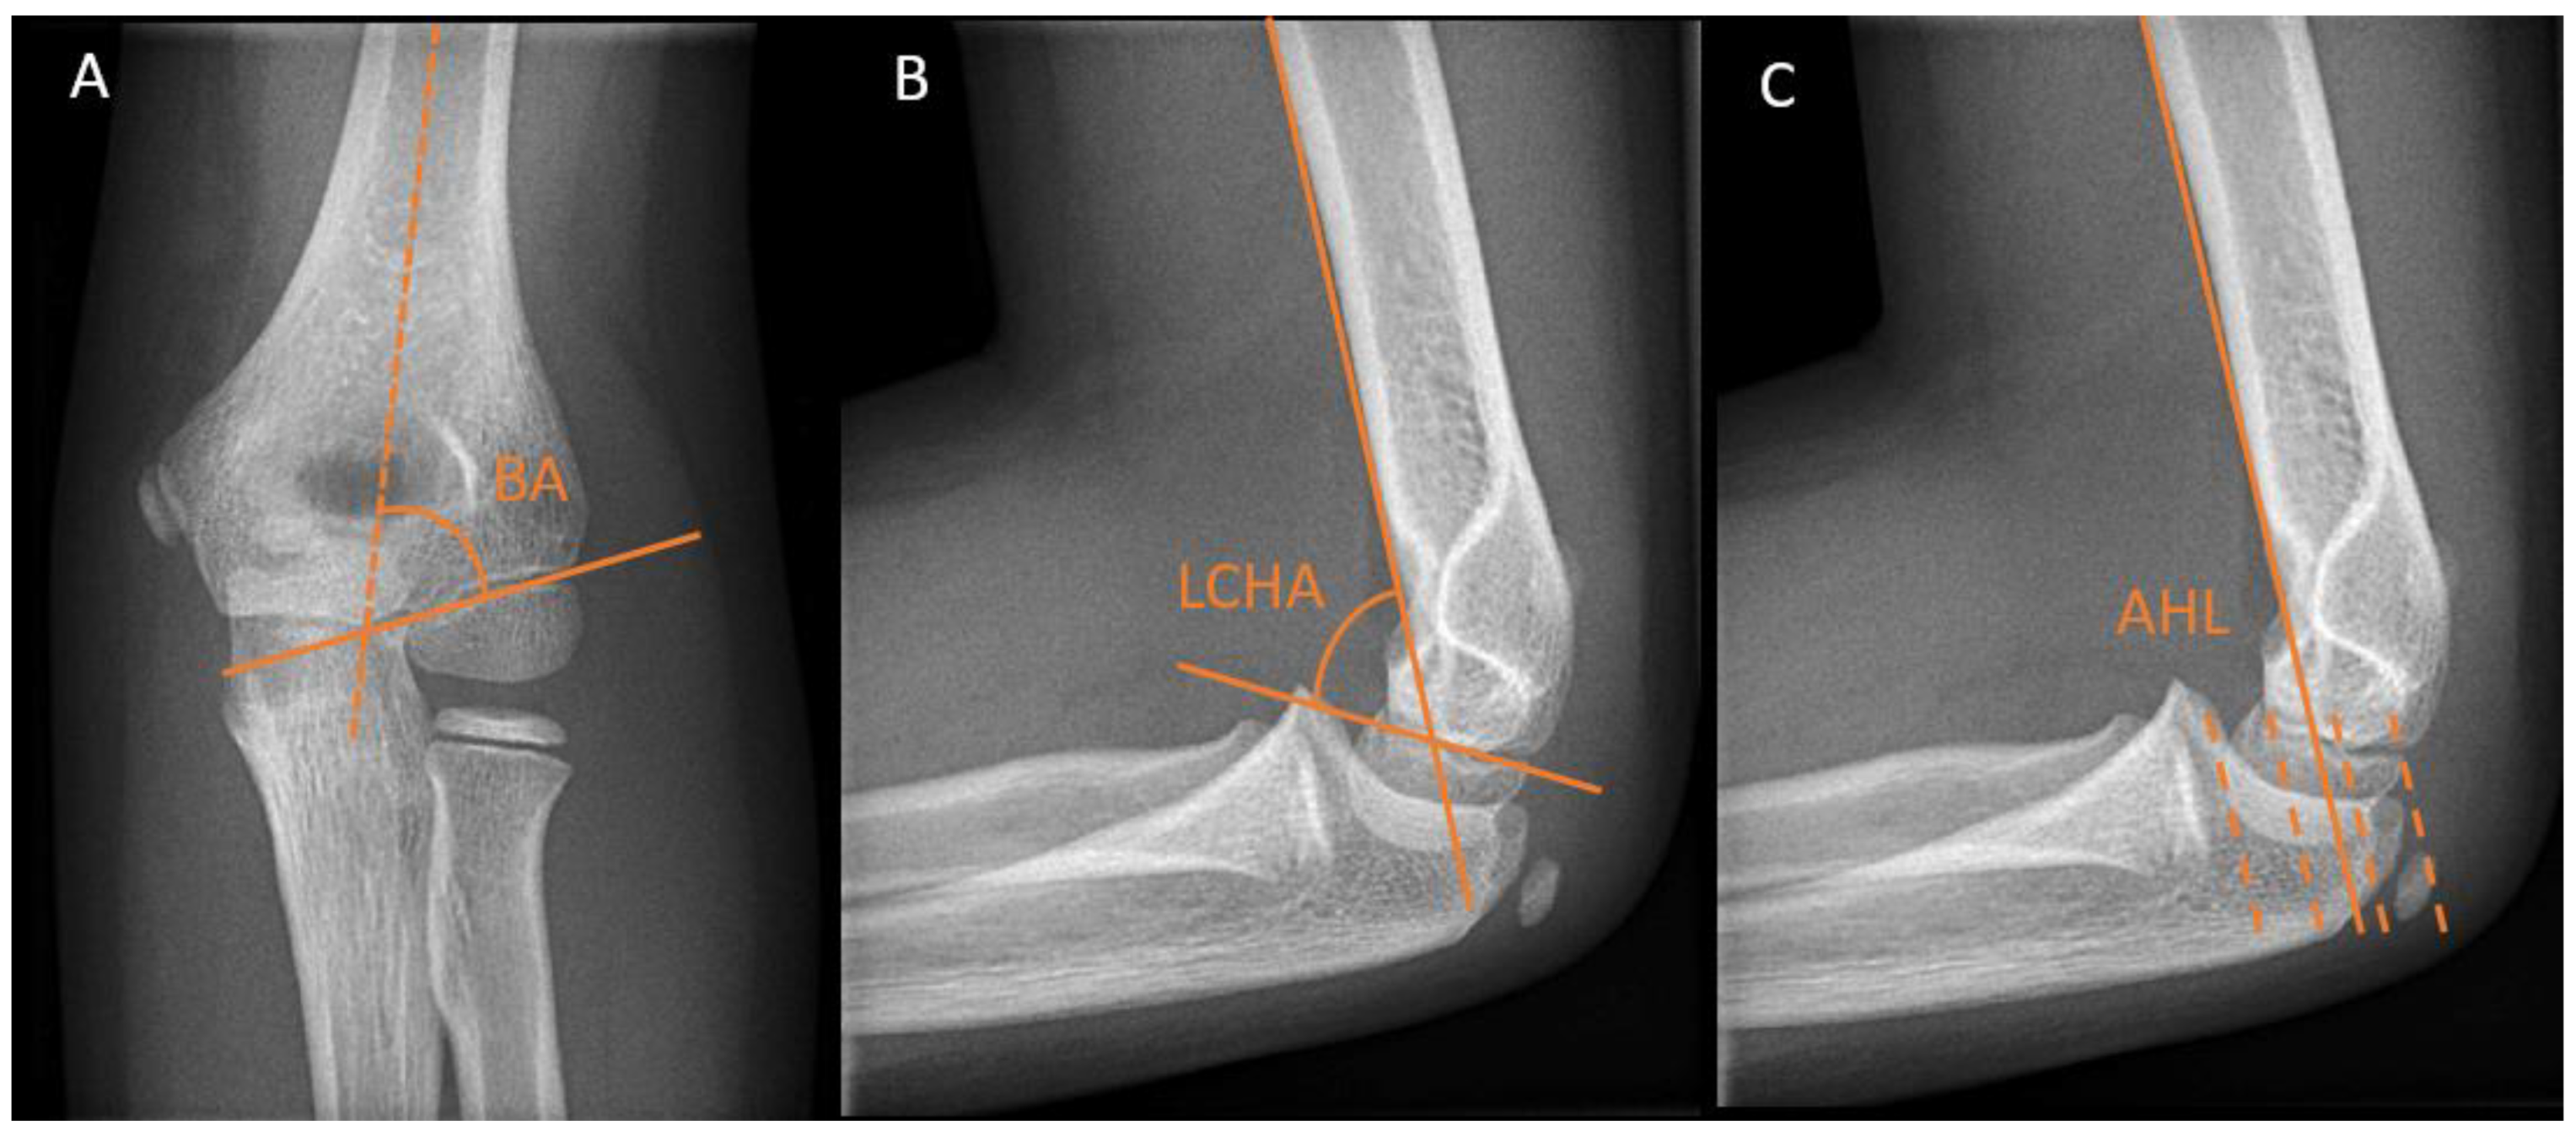

Different radiographic angles have been described for the assessment of humeral alignment. The Baumann’s angle is measured on an anteroposterior (AP) radiograph with the elbow in extension. It is formed by the angle between the long axis of the humeral shaft and a straight line through the epiphyseal plate of the capitellum or the lateral condylar physis (Figure 2A). There is a considerable variation in individuals, ranging from 64 to 82 degrees [10,11]. Therefore, the Baumann’s angle is best compared to the contralateral side, where a difference >5 degrees is deemed abnormal.

The lateral capitellohumeral angle (LCHA) is measured on a lateral radiograph as the angle between the line along the anterior surface of the humerus and a line along the open capitellar physis (Figure 2B). The LCHA has a smaller normal range from 45 to 57 degrees and does not vary by age, side, or sex [12] (Figure 2B).

The lateral anterior humeral line (AHL) or capitellohumeral line is a line drawn along the anterior surface of the humerus, which should pass through the middle third of the capitellum on a lateral view (Figure 2C).

Figure 2. Distal humerus radiographic reference lines. (A) Baumann angle (BA) on an anteroposterior elbow view. (B) The lateral capitellohumeral angle (LCHA) on a lateral elbow view. (C) Anterior humeral line (AHL) on a lateral view. This line should pass between the two dotted lines in the middle.